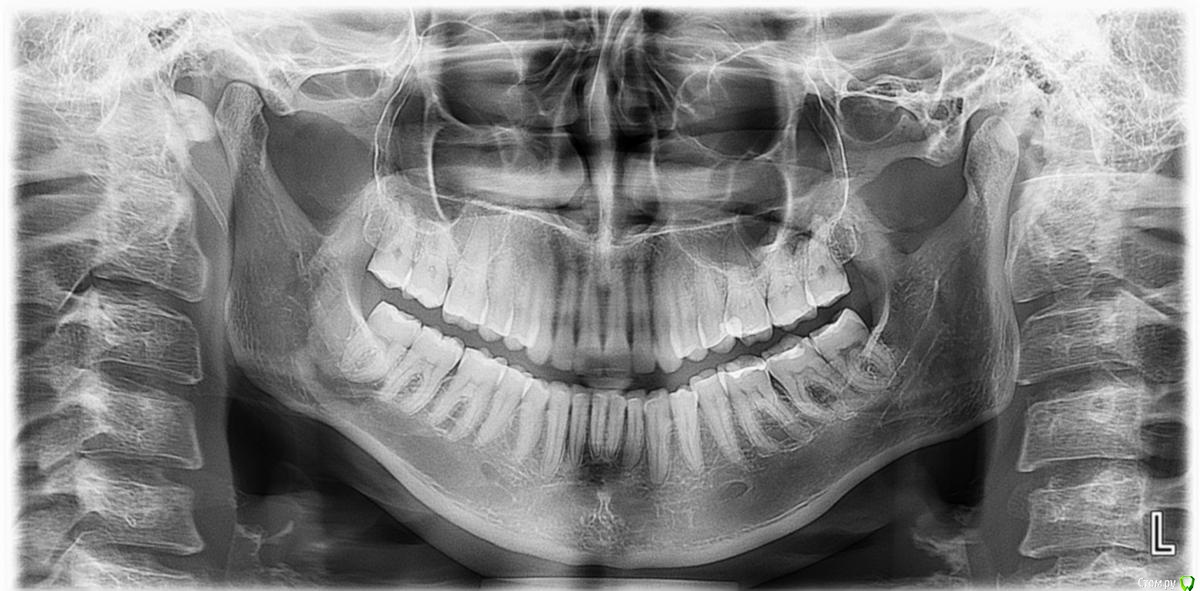

chuvashova_mv Опубликовано 18 июня, 2016 Поделиться Опубликовано 18 июня, 2016 (изменено) Мне 31 год. Тюмень. Сильное оголение корней каждого зуба. Сосочки на месте. Карманов нет. Тонкий биотип десны. Была у неск.ортодонтов, дело не в прикусе.Эндокринолог значит.отклонений не видит (щитовидка в норме, сах.диабета нет, менстр.регулярная сейчас, раньше были сбои), только имт 16,5. Есть ребёнок 3 года, заберем. сама.Гастроэнтеролог - хр.гастродуоденит со школы, желудок работает не в полную меру.Неврология - всд по гипотония.типу., бруксизма нет.Очень сух.кожа с рождения, особенно тяжко зимой.Прилагаются кт и оптг.Вопрос: все очень плохо? У нас в городе вызвались только два врача оперировать, но таких случаев как у меня у них не было.Нужна помощь пародонтологов-хирургов, кто с таким сталкивался. Изменено 18 июня, 2016 пользователем chuvashova_mv Ссылка на комментарий

faity Опубликовано 20 июня, 2016 Поделиться Опубликовано 20 июня, 2016 Судя по ОПТГ дисфункция и деформация ВНЧС, гипертрофия жевательной мускулатуры слева.По фото множественные рецессии и патологическая стираемость зубов.У вас классическая окклюзионная травма которая дала рецессию, стираемость, щелчки в суставе(если уже появились). Вам гнатолог нужен для начала ибо у вас причину сложнее устранить чем последствия в виде стираемости и рецессий.Зубы сжимаете во сне или во время бодроствования? 2 Ссылка на комментарий